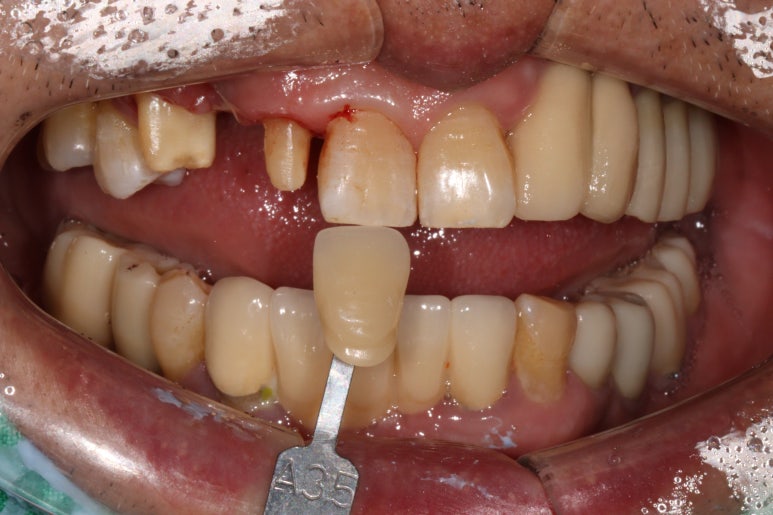

이를 제거하고 앞니 브릿지를 제작하기 위해 치아 삭제를 시행하였습니다.

shade guide를 사용하여 치아의 색상을 측정하였습니다.

A3.5를 적용하니 조금 어두우나 치경부와는 비슷한 색을 내네요.

치아가 다양한 색상을 갖고 계시기 때문에 최대한 자기 치아를 모방하기 위해 꼼꼼하게 치아색상을 기록합니다.

앞니 지르코니아 브릿지 제작을 위해

치아를 삭제하고 뽄을 떠 1주일 뒤에 최종 보철물을 연결합니다.